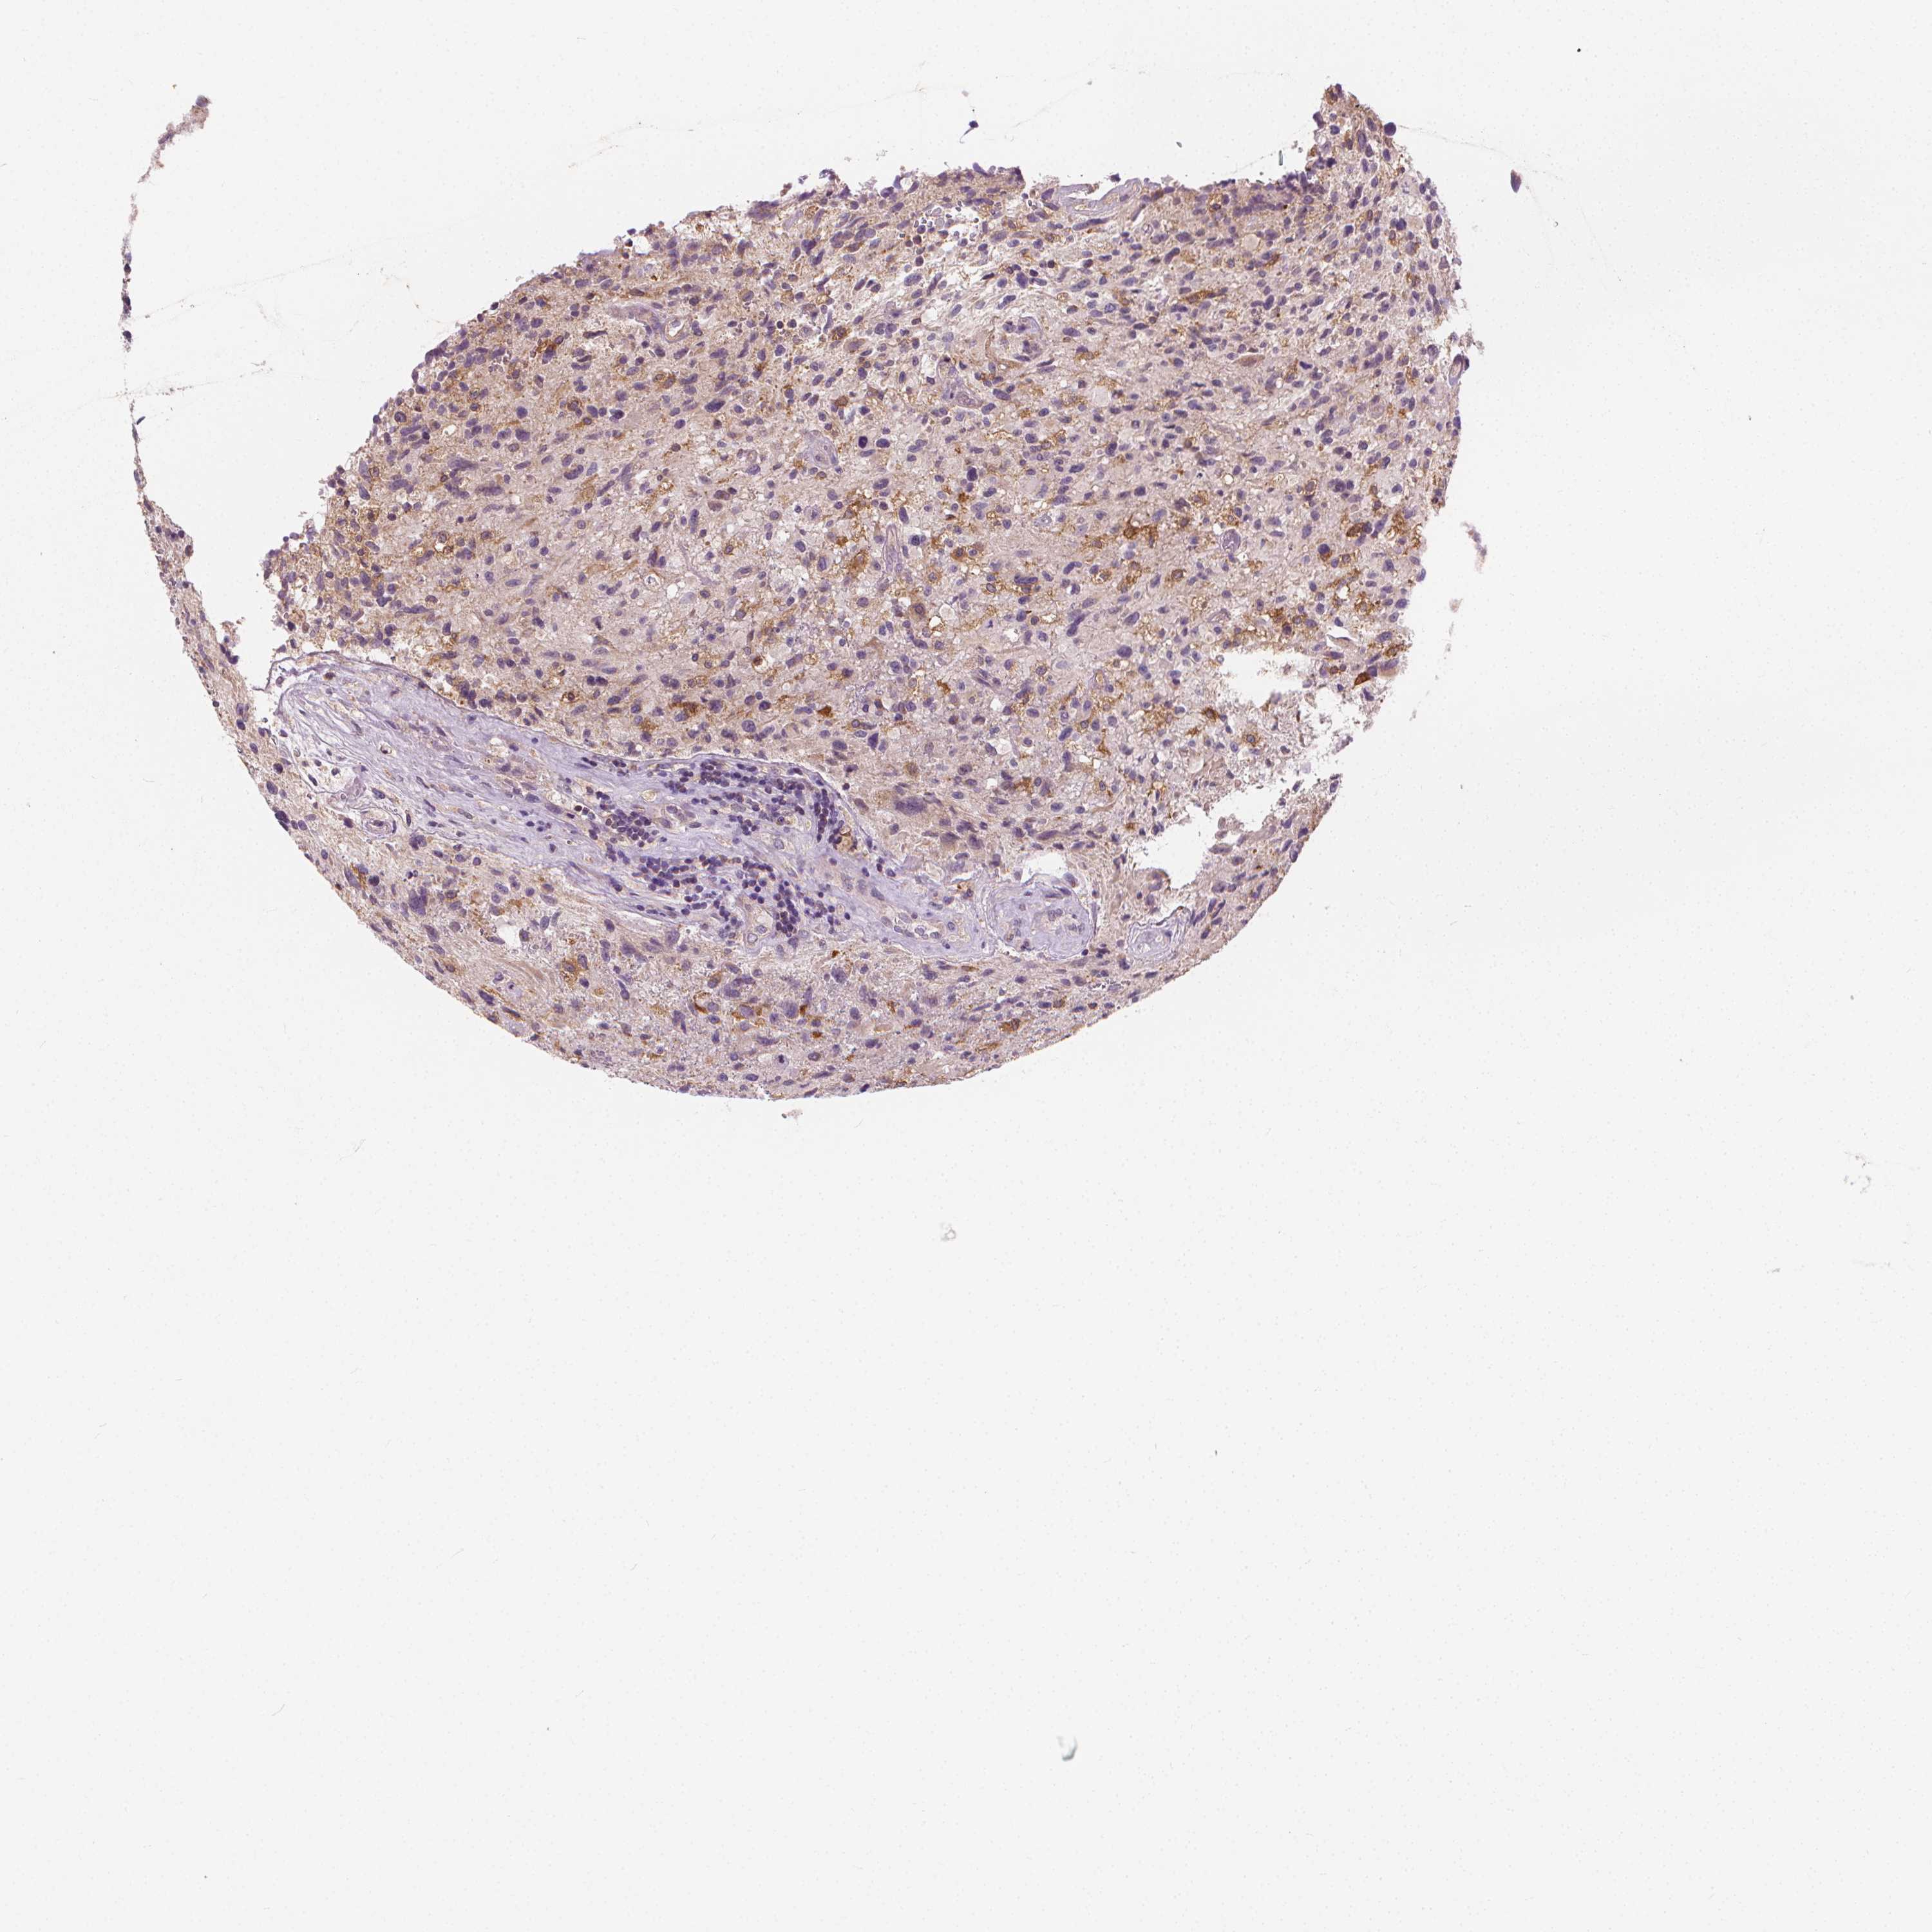

GLIOMA - Protein expressioni

A mouse-over function shows sample information and annotation data. Click on an image to view it in a full screen mode. Samples can be filtered based on level of antibody staining by selecting one or several of the following categories: high, medium, low and not detected. The assay and annotation is described here.

Note that samples used for immunohistochemistry by the Human Protein Atlas do not correspond to samples in the TCGA dataset.

Antibody stainingi

Antibody staining in the annotated cell types in the current human tissue is reported as not detected, low, medium, or high, based on conventional immunohistochemistry profiling in selected tissues. This score is based on the combination of the staining intensity and fraction of stained cells.

Each image is clickable and will lead to virtual microscopy that enables deeper exploration of all samples and also displays staining intensity scores, fraction scores and subcellular localization as well as patient and tissue information for each sample.

Antibody HPA068647

Staining

High

Medium

Low

Not detected

Intensity

Strong

Moderate

Weak

Negative

Quantity

>75%

75%-25%

<25%

None

Location

Nuclear

Cytoplasmic/membranous

Cytoplasmic/membranous,nuclear

Glioma, malignant, Low grade

Glioma, malignant, High grade